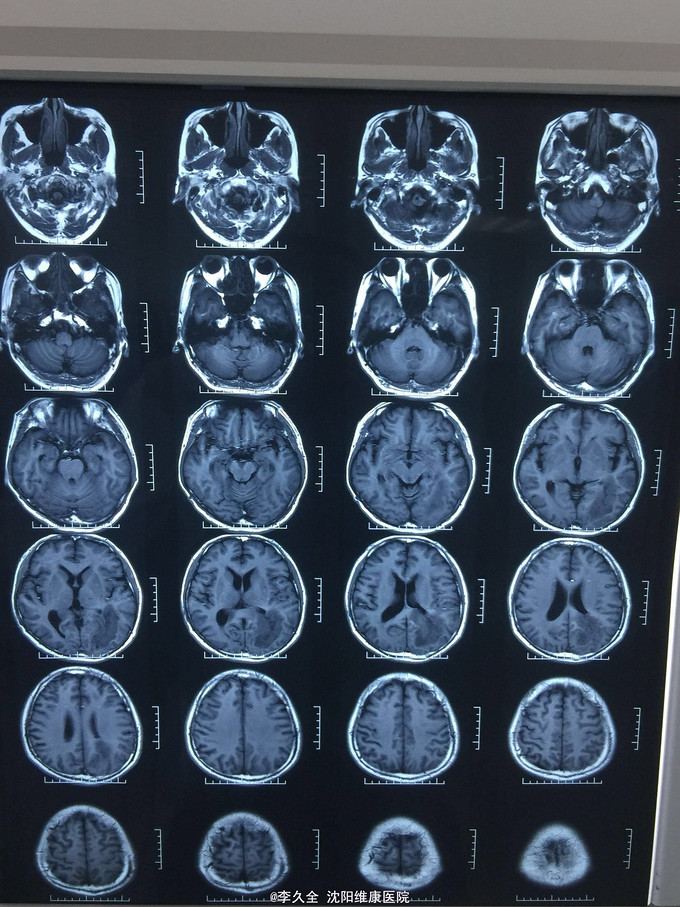

男,62岁,以头晕、视野缺损、记忆力减退、失写、失算7个月入院! 现病史:去年7月出现头晕,就诊于医院,行头CT:代诉未见异常,口服药物无效,后出现右侧视野缺损,走路撞墙、撞门,就诊于当地医院、北京协和医院,考虑“㬵质瘤”,近3个月出现近事遗忘为主,平时写字不会,计算力下降,不认识人! 既往史:2型糖尿病5年!

查体:BP:150/80mmHg,心肺腹无异常。神清,不能言语,失写、失算、失认,双曈孔等大正圆,直径3.0mm,光敏,四肢能够活动,右侧肌张力增高,巴氏征R+L-,颈强3横指,克氏征阳性! 影像MR:

1.颅内占位,胶母可能大! 2.2型糖尿病